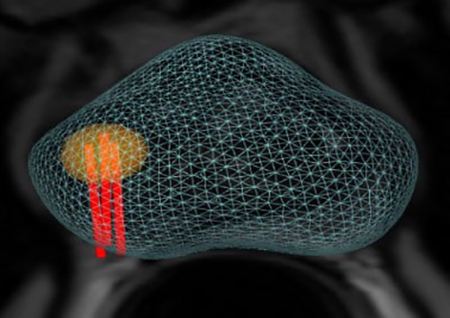

Koelis Trinity Perine

Υπερσύγχρονη πλατφόρμα πλοήγησης που επιτρέπει:

- Την ελαστική συγχώνευση τρισδιάστατων εικόνων Υπερηχογραφήματος και Μαγνητικής Τομογραφίας σε πραγματικό χρόνο μέσω του λειτουργικού συστήματος εντοπισμού Organ-Based Tracking Fusion( OBT Fusion).

- Aπεικόνιση του προστάτη σε τρισδιάστατη μορφή.

Ακολουθούν Εικόνες

TRINITY PERINE

OBT FUSION

OBT FUSION